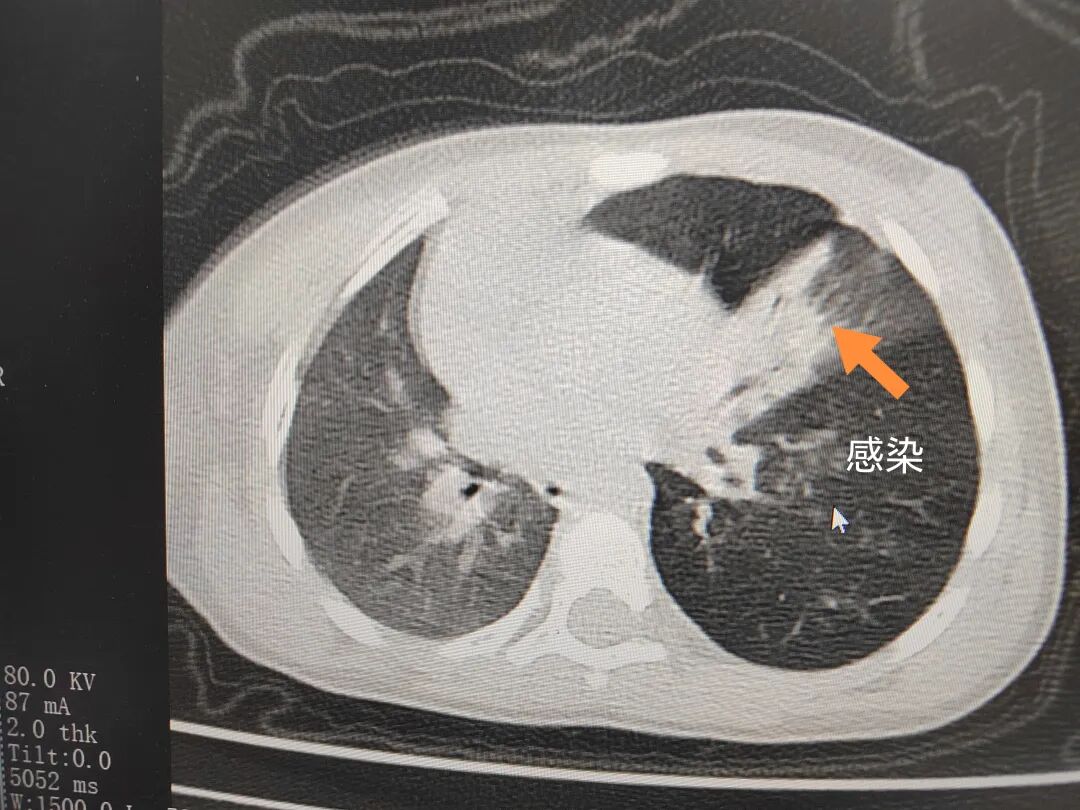

三天后(11月13日),趙寶出現(xiàn)高熱、咳喘加重,家長(zhǎng)著急了,再次帶他來(lái)到醫(yī)院。CT檢查顯示左肺過(guò)度充氣,左肺上下葉支氣管主干見(jiàn)不規(guī)則高密度影,左肺上葉可見(jiàn)大片狀密度增高影,縱隔窗實(shí)變,提示為“左側(cè)支氣管內(nèi)異物并繼發(fā)性改變,左肺上葉舌段肺膨脹不全”。

市二院小兒呼吸內(nèi)科團(tuán)隊(duì)迅速為患兒制定了周密的手術(shù)方案,并很快安排了氣管鏡探查。術(shù)中,主治醫(yī)師田慧等憑借嫻熟的氣管鏡操作技術(shù)成功將異物大塊板栗取出。由于板栗在氣管內(nèi)存留時(shí)間較長(zhǎng),質(zhì)地軟糯易碎,大大增加了手術(shù)難度。檢查還發(fā)現(xiàn),異物停留部位的氣管黏膜已出現(xiàn)充血紅腫、糜爛,導(dǎo)致患兒住院時(shí)間相應(yīng)延長(zhǎng)。此次事件給趙寶的家庭帶來(lái)了不小的驚嚇與擔(dān)憂,也再次為廣大家長(zhǎng)敲響了警鐘。

市二院小兒呼吸內(nèi)科副主任楊亞娟介紹,異物誤入氣道可能導(dǎo)致氣道阻塞,嚴(yán)重時(shí)可引發(fā)窒息,甚至危及生命。若異物進(jìn)入支氣管,造成不完全堵塞,可引起阻塞性肺氣腫;如完全堵塞支氣管,則可能導(dǎo)致肺組織萎縮,形成肺不張。此外,若異物存留時(shí)間較長(zhǎng),或?yàn)橹参镄援愇?,容易合并?xì)菌感染,產(chǎn)生膿性分泌物,進(jìn)而發(fā)展為肺炎。她強(qiáng)調(diào),盡早診斷并取出異物,是減少并發(fā)癥、降低病死率的關(guān)鍵。